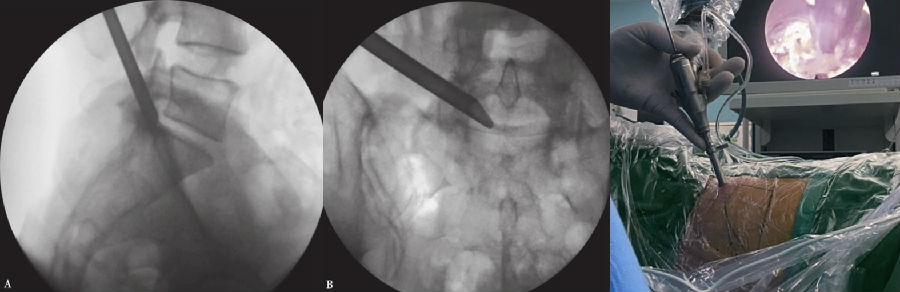

8. 镜下操作

采用一次性双极射频手术刀头、Punch钳、小直钳、磨钻依次切除或修整部分肥厚或钙化的黄韧带、椎体后缘增生的骨赘、椎体后缘对神经根造成压迫的外层纤维环及其边缘的硬化或骨化结构、与后纵韧带粘连的增生结缔组织,对神经根背侧和腹侧进行全面的减压松解,特别是神经根下方的微小硬化性组织。(图16~图21)

图16 内镜下显示套管内视野中间纤维环

图17-图20 内镜下显示套管内视野中间纤维环;内镜下小直钳取髓核;取出部分髓核后张力下降,神经张力间接下降;转动工作套管显露硬膜囊和周围组织

9. 双极射频使破裂的纤维环消融皱缩成形。观察可见硬膜囊自主搏动,神经根表面血运明显改善,血管充盈,神经根复位,术中行直腿抬高试验,可见神经根被牵拉后滑移自如。(图22、图23)

10. 旋转工作套筒检查视野内无出血、残余碎片等,确认无异常后移除内镜及工作套管。切口缝合1~2针。(图24)

图21-图24 取出的髓核组织(中间部分硬化);下行根头端减压;硬膜囊、下行根减压后神经松解,博动良好;手术切口(大小约8mm)